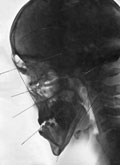

Телерентгеннограмма в прямой и боковой проекциях. Сочетанная деформация лицевого черепа, синдром «длинного лица».